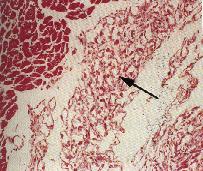

心肌呈蒼白,紅白相間,主要出現於心室或心房肌肉層,房室瓣。病變常呈多發,有時可見腫大組織向心內膜生長,突出於心室壁。 三、 組織病變: 病變多發,常見於心包膜下方,心內膜下方或心肌間。特徵為許多小結節,外圍

為正常心肌纖維,結節內為許多腫大空泡樣細胞,間雜有微血管,大多數細胞為 HE

染色陰性,PAS 染色陽性。細胞核呈卵圓形,位於細胞中央或周圍。偶而可見不完整

的橫紋出現細胞質中。四、 討論及參考文獻: (一)討論: 橫紋肌增生症 常見於天竺鼠之心肌層,非腫瘤性疾病。又稱congenital rhabdomyoma, congenital